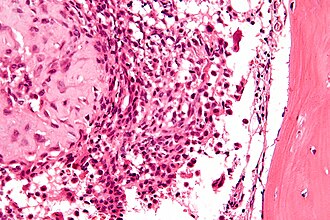

Chondroblastoma. H&E stain. | |

| LM | abundant (chondroid) extracellular material, chondroblasts (variable nuclear morphology (ovoid, folded or grooved), moderate-abundant eosinophilic cytoplasm), +/-calcifications surrounding the cell nests ("chickenwire" appearance) - classic feature, +/-giant cells |

- Abundant extracellular material - pink on H&E stain - looks vaguely like cartilage.

- Sometimes described as 'immature cartilage' (very narrow DDX for this type of cartilage)

- Chondroblasts:

- Nuclear morphology variable: ovoid, folded or grooved.

- Moderate-abundant eosinophilic cytoplasm.

- +/-Calcification surrounds the cell nests ("chickenwire" appearance) - classic feature.

- Cell nests have a thin pale blue rimming.

- +/-Giant cells.